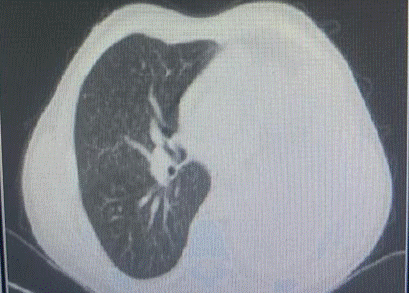

Inicia su padecimiento en octubre de 2014, de manera insidiosa con tos productiva, acompañada de expectoración blanquecina, sin predominio de horario. La tos se intensificó durante el día y ocasionalmente interrumpió el sueño nocturno. Una semana después aparecieron episodios esporádicos de hemoptisis, descritos como expulsión de pequeñas cantidades de sangre fresca mezclada con expectoración. Estos síntomas se acompañan de fiebre de predominio vespertino, escalofríos ocasionales y sudoración profusa nocturna. De forma paralela, presentó astenia, adinamia, hiporexia y pérdida de peso no intencionada de aproximadamente 7 kg en pocas semanas. Agregándose dolor torácico infraclavicular derecho, exacerbado por inspiración profunda y la tos, sin alivio significativo con el reposo o analgésicos. Persistieron la tos, la disnea leve a esfuerzos moderados y los episodios ocasionales de hemoptisis, motivo por el cual acudió a valoración médica. Sin antecedentes personales de enfermedades respiratorias crónicas o contacto con personas con tuberculosis ni viajes recientes, se decidió su hospitalización para protocolo de estudio. Realizándose de manera inicial tomografía axial computarizada (TAC) de tórax inicial, la cual reveló una imagen sugestiva de proceso neoplásico en el lóbulo superior pulmonar izquierdo. Posteriormente, en noviembre de 2014 se efectuó broncoscopia diagnóstica, evidenciándose una lesión tumoral endobronquial de la cual se tomaron biopsias dirigidas, cuyo resultado fue neoplasia maligna epitelial de alto grado, ulcerada y necrosada, del tipo células aveniformes. El 8 de diciembre de 2014, un nuevo estudio anatomopatológico confirmó la presencia de neoplasia maligna poco diferenciada, compatible con carcinoma de células pequeñas de pulmón, con abundante necrosis y una reacción linfocítica prominente. El 17 de febrero de 2015, una nueva TAC de tórax realizada en el Hospital General de Zona No. 1 mostró opacificación total del parénquima pulmonar izquierdo, compatible con progresión neoplásica (Figura 1), así como múltiples lesiones micronodulares de distribución intersticial en el pulmón derecho, sugestivas de linfangitis carcinomatosa (Figura 2). Los hallazgos radiológicos fueron además compatibles con neumoconiosis silicótica. Confirmado el diagnóstico, el paciente fue referido al servicio de Oncología, donde inició tratamiento especializado con radioterapia. La evolución radiológica evidenció progresión tumoral y compromiso bilateral con patrón micronodular difuso.

Figura 2.

Radiografía posteroanterior de tórax.

Nota: Hemitórax izquierdo con opacidad casi completa, borramiento de ángulos costodiafragmáticos, desplazamiento del mediastino al lado contralateral.

El paciente presentó una exposición ocupacional prolongada de 29 años a polvo de sílice cristalina respirable, sin uso adecuado uso del sistema de gestión de riesgos, desarrollando neumoconiosis por sílice y posteriormente carcinoma pulmonar de células pequeñas. Los estudios de imagen iniciales evidenciaron una opacidad total del pulmón izquierdo acompañada de lesiones micronodulares en el pulmón derecho, signos radiológicos compatibles con neumoconiosis. El diagnóstico por medio de anatomía patológica confirmó, mediante biopsia bronquial, una neoplasia maligna epitelial de alto grado, variedad células aveniformes, con abundante necrosis y reacción linfocítica prominente.